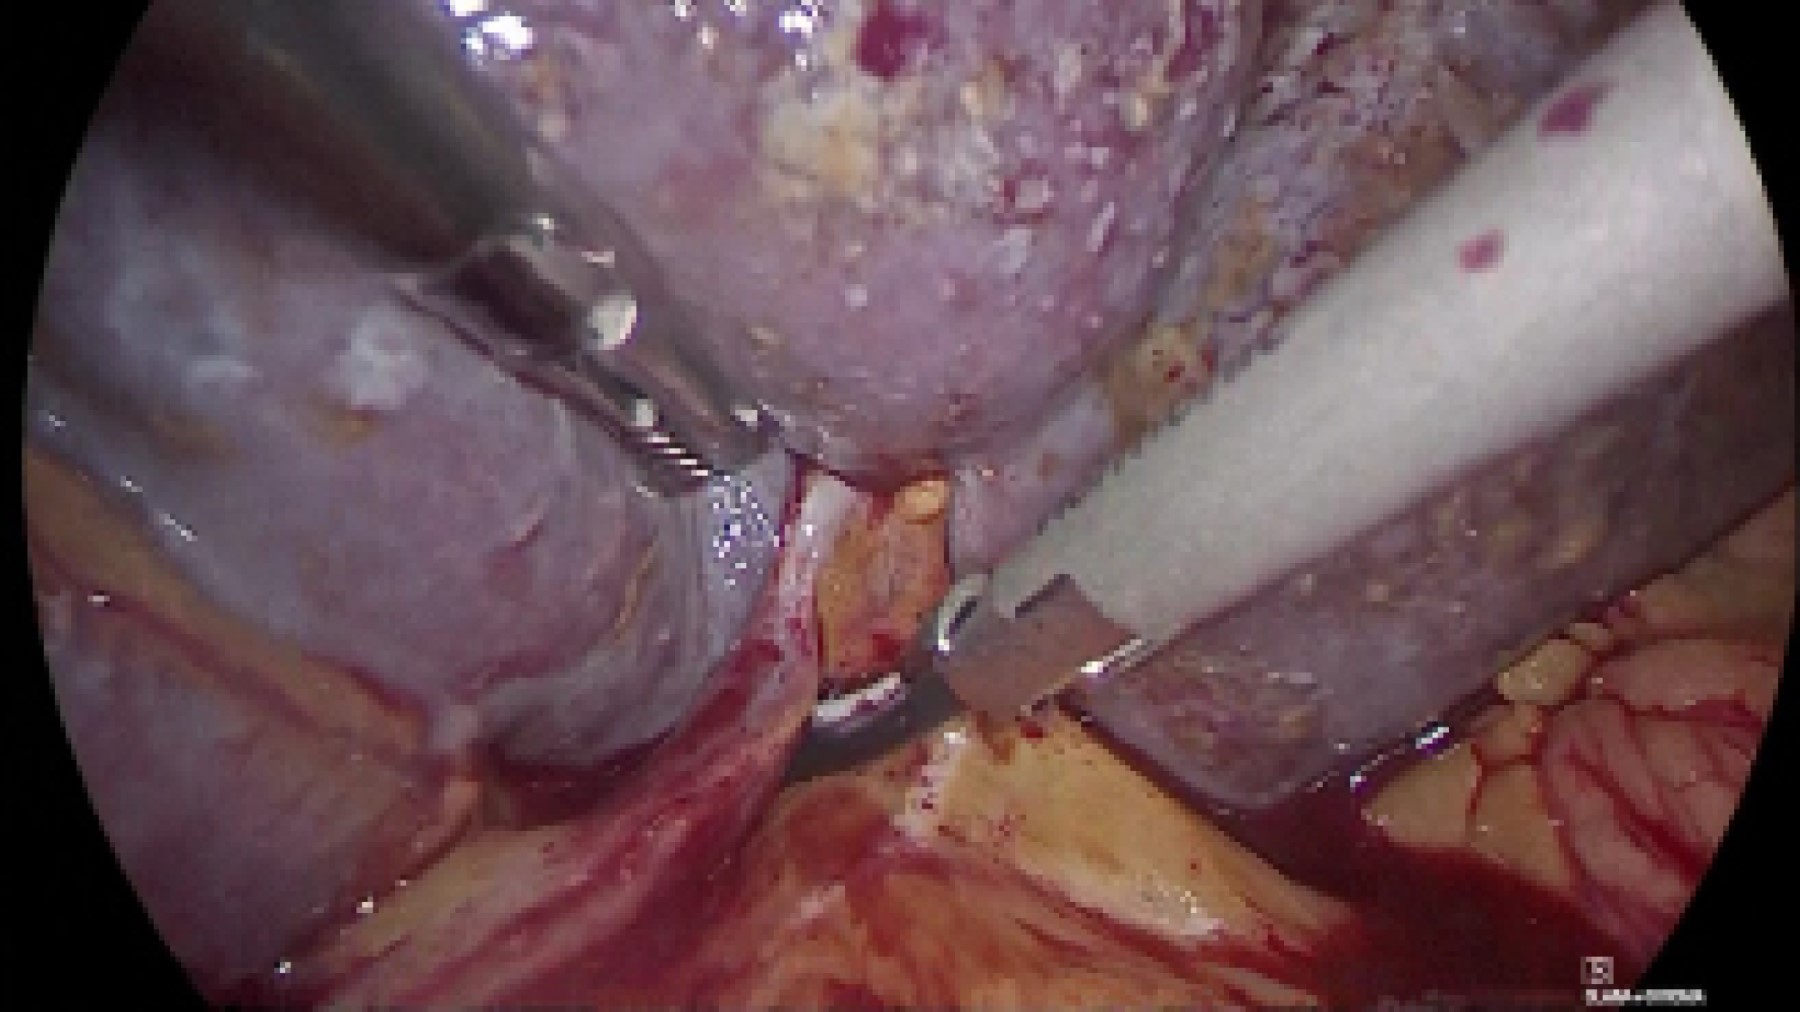

Al introducir el video-laparoscopio se encontró hemoperitoneo de tres litros aproximadamente, esplenomegalia y ruptura de la cápsula, aspecto moteado y sangrado activo (Figura 2); el hígado se observó con apariencia cirrótica y datos de hipertensión portal con sistema venoso colateral umbilical. Ante los hallazgos y la obesidad del paciente, por el espacio reducido, se hizo incisión de 9 cm en flanco izquierdo para retractor mediano (5-9 cm) para continuar procedimiento mano asistida con levantamiento de bazo y mejor control vascular. Además de bisturí armónico (Figura 3), se usó endograpadora vascular de 45 mm para los vasos esplénicos y vasos cortos, debido a su grosor. Se dejaron hemostáticos en lecho esplénico, se visualizó sangrado hepático en capa, y a causa de las condiciones hemodinámicas y de coagulopatía de consumo, se decidió empaquetamiento hepático con compresas introducidas a través de puerto mano asistida, se colocaron dos superiores al hígado y una inferior. Se colocó drenaje cerrado subfrénico izquierdo, se finalizó evento quirúrgico, trasladando al paciente a la unidad de cuidados intensivos (UCI), la pieza midió 24 cm (Figura 4). Durante las primeras horas posquirúrgicas disminuyó gasto hemático por drenaje y mejoró estabilidad hemodinámica.

Figura 2

Figura 3